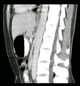

Superior mesenteric artery (SMA) syndrome is a gastro-vascular disorder in which the third and final portion of the duodenum is compressed between the abdominal aorta (AA) and the overlying superior mesenteric artery. This rare, potentially life-threatening syndrome is typically caused by an angle of 6°–25° between the AA and the SMA, in comparison to the normal range of 38°–56°, due to a lack of retroperitoneal and visceral fat (mesenteric fat). [Source: Wikipedia ]